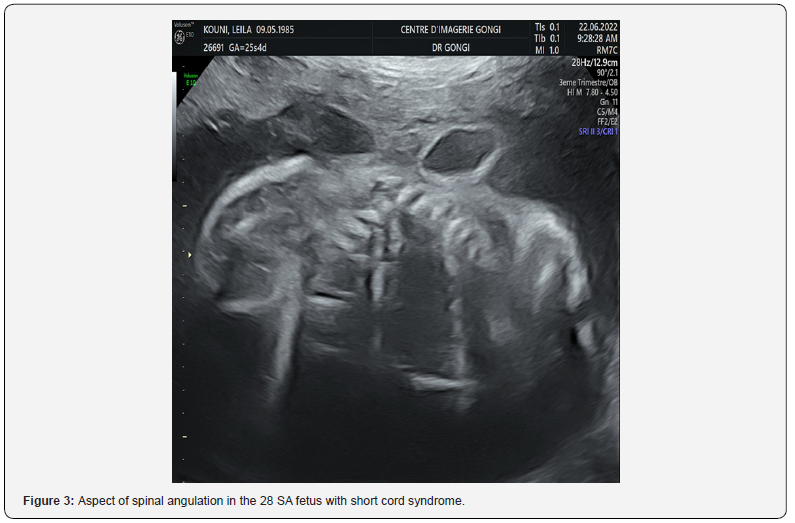

Obstetrical ultrasound revealed an evolving mono-fetal pregnancy, with amitotic fluid in diminished quantity, a cerebral floor without anomalies (Figure 1), a large coelosomycompléte, heart, liver and intestine bathed in amniotic fluid, (Figure 2) without individualization of the diaphragm, with anomalies of the spine (Figure 3) anomalies of the lower limbs, a right clubfoot. The fetus appeared to be attached to the placenta. An umbilical cord containing two arteries and a very short vein (Figure 4), The most likely diagnosis was short cord syndrome. After discussion with the parents and a psychological interview with the woman, the pregnancy was terminated. Macroscopic examination at birth revealed a male fetus weighing 500g, with a marked anterior complete coelosomy (heart, liver and intestine exteriorized). Narrow thorax. The spine is angulated, and the lower limbs are club-footed (Figure 4). The fetus was attached to the placenta by a very short 6 cm cord, with 2 arteries and one vein (Figure 5). The fetus was pathologically examined for other visceral malformations. However, all the ultrasound findings and macroscopic examination (Figure 6) enabled the diagnosis to be accepted.

An abnormally inseparable fetus (partially attached to the placenta). Absence of umbilical cord or very short cord. Large thoraco-abdominal wall defect (vast celosomy - coelosomy) in the form of a complete thoraco-abdominal evisceration not covered by a membrane. Sometimes the peritoneum fuses with the amnion (amnionperitonealsleeve). Defects of the thoraco-abdominal wall may be associated with diaphragmatic hernia or absence of the diaphragm; defect of the sternum and also cardiac malformations, in particular ectocardia (ectocardia - ectopiacordis). Visceral anomalies: intestinal atresia; renal malformations such as pyelectasis, renal agenesis, renal cystic dysplasia. Anomalies of the spine, such as scoliosis or kyphoscoliosis (sometimes with several points of angulation) and reduction anomalies of the spinal column (caudal regression). The neck is often elongated. Lower limb anomalies: club feet, reduction anomalies (absence of limbs or toes); polydactyly, syndactyly, arthrogryposis...